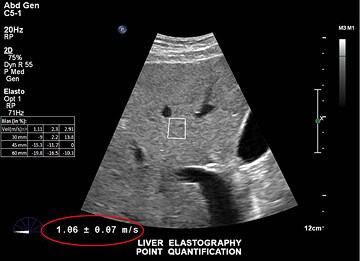

Einfachere nichtinvasive Beurteilung der Lebersteifigkeit Mit der Scherwellen-Elastographie von Philips lässt sich die Lebersteifigkeit auch bei schwer schallbaren Patienten überraschend schnell und einfach messen. Dieses nichtinvasive, anwenderfreundliche Verfahren erfordert nur einen schnellen Handgriff für Sonografiker und ist für Patienten nahezu schmerzlos.

Die Philips Elastographie erzeugt Scherwellen in der Leber mittels Schallkraft durch einen fokussierten Ultraschallstrahl. Das System überwacht die Ausbreitung der Scherwellen, misst ihre Geschwindigkeit und zeigt sie dann in einem leicht zu befundenden Format an.

Durch einen einfachen, nichtinvasiven Scan wird die Lebersteifigkeit in Sekundenschnelle gemessen.